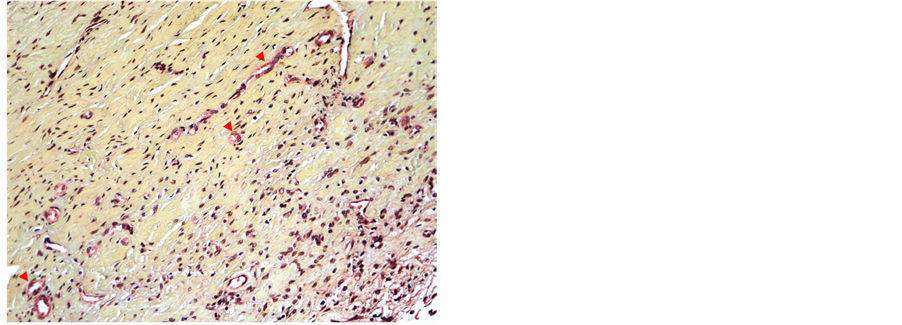

Eight weeks after the operation, inflammatory processes in the neodura had regressed further. MP-stained slides showed neogenesis of tissue and emerging new blood vessels (angioneogenesis). The subarachnoid space was again evident in the periphery, but directly below the graft site mononuclear inflammatory infiltrates are still evident (Figure 11 and Figure 12).

Figure 11. Graft 8 weeks postoperatively showing dura with dense collagen fibers (yellow-green), fibroblasts and newly formed capillaries (arrowheads). Mild perivasular mononuclear inflammation (MP-staining, 20× objective).

Figure 12. Brain 8 weeks postoperatively. Subarachnoid space partly filled with mononuclear leukocytes (*) (HE- staining, 4× objective).